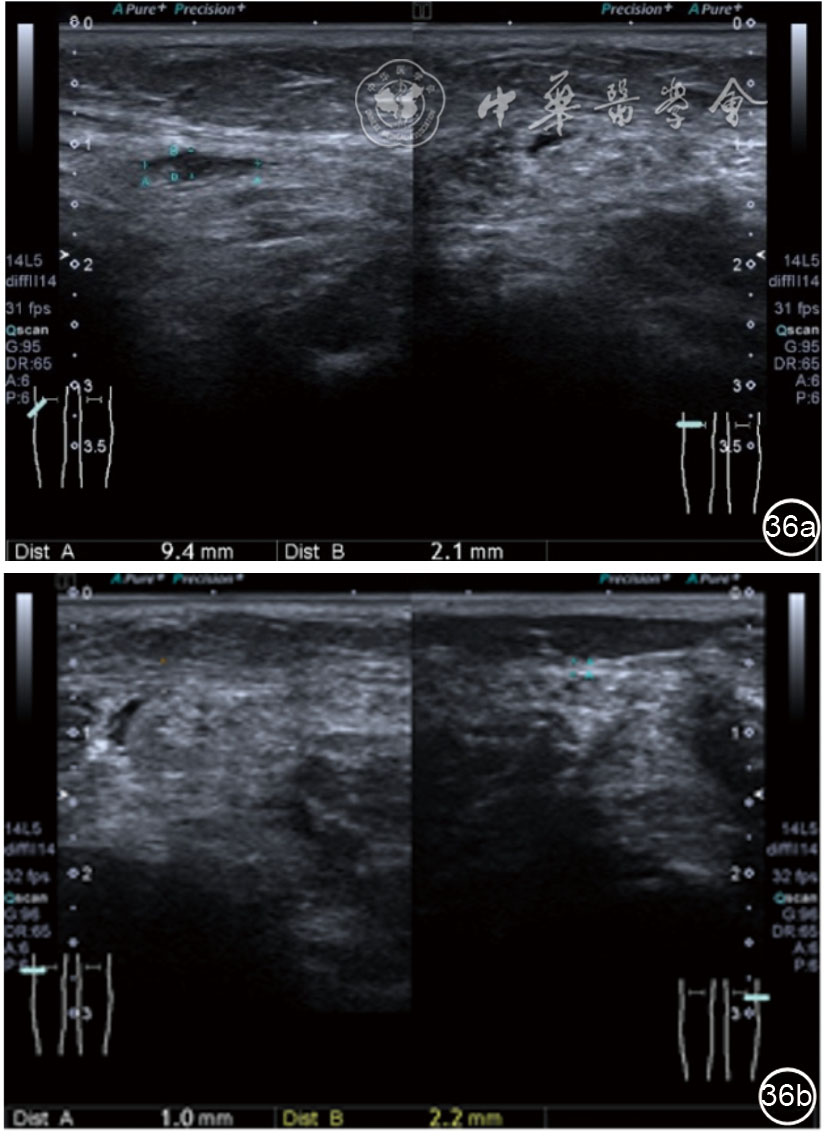

3.超声半定量评估。(1)骨赘超声半定量评估:患者仰卧位,膝关节伸直,探头纵切面置于膝关节内侧与外侧,自前向后移动探头以进行全面扫查。测量骨赘的厚度,并进行半定量分析。0级:无骨赘;1级:小骨赘,厚度<2 mm;2级:中等骨赘,厚度2.1~4.0 mm;3级:大骨赘,厚度>4.0 mm。(2)关节软骨超声半定量评估:患者仰卧位,膝关节完全屈曲。探头置于骨上方,检查股骨内侧髁、外侧髁和股骨滑车处关节软骨三个部位,分别进行横切面和纵切面检查,从近侧向远侧做全面扫查。检查时声束要垂直于股骨表面。关节软骨可按病变严重程度分为四级。0级:关节软骨呈均匀的无回声带,其浅侧和深侧边界清晰。1级:关节软骨浅侧边界不清和(或)内部回声增高。2级:①2A级,关节软骨局部变薄,缺损厚度<50%;②2B级,关节软骨局部变薄,缺损厚度>50%,但<100%。3级:关节软骨局部完全消失,伴或不伴有软骨下骨病变。(3)半月板突出分度:半月板外周缘与胫骨平台边缘之间的距离≥3 mm的突出视为病理变化,诊断为半月板周缘滑脱。按照突出程度分为三度:Ⅰ度,半月板外周缘与胫骨平台边缘之间的距离3~5 mm;Ⅱ度,半月板外周缘与胫骨平台边缘之间的距离>5~8 mm;Ⅲ度,半月板外周缘与胫骨平台边缘之间的距离8 mm以上。

患者采取侧卧位,患肢在上,屈膝20°。应用10~18 MHz高频线阵探头,扫查深度1~3 mm。长轴和短轴结合双侧对比扫查。超声影像学所见:短轴可见卡压腓总神经近端增粗,面积增大;长轴可见腓总神经卡压处变细,其近侧肿胀、回声减低,而在卡压远侧则表现正常(图35);一些受压严重者可以出现神经周围积液,卡压神经部位的筋膜增厚(图36);受压神经内血流增加对临床诊断意义更大(图37);探头在病变神经处加压常可引起神经刺激症状。腓总神经支配的肌肉有失神经支配改变,表现为肌肉回声增高和肌肉萎缩(图38)。

图36 超声图像示腓总神经周围积液,卡压神经部位的筋膜增厚